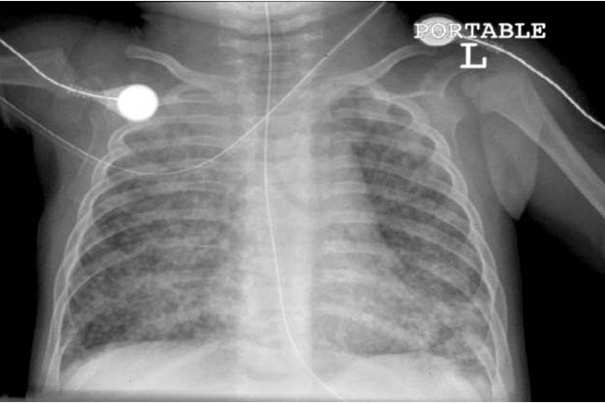

A chest X-ray of a child whose lungs are being damaged by tuberculosis. Researchers now estimate that approximately 1 million children contract TB annually.

Courtesy of Jeffrey Starke